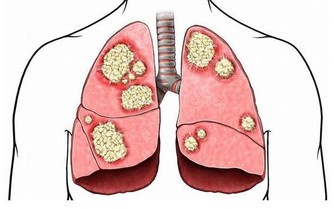

艾滋病傳播的途徑主要是:與感染者的血液、乳汁、精液、陰道分泌物等多種體液發生交換。